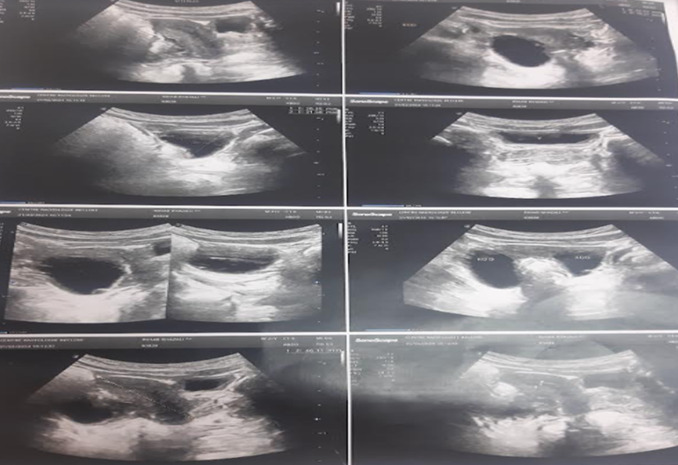

McCune-Albright Syndrome is a rare condition with a clinical diagnosis, typically suspected when the classic triad is present: café-au-lait spots, fibrous dysplasia of bone and endocrinopathy. Therapeutic management depends on the endocrine involvement and the severity of bone disease. We here report an original case of a 2-year and 8-month-old girl presenting with precocious puberty revealing McCune-Albright syndrome. The diagnosis was suspected due to premature menarche and premature thelarche associated with café-au-lait spots. Biochemically, estradiol levels were elevated at 179 ng/ml with low FSH and LH levels. ALHRH test demonstrated a flat FSH LH profile with a peak LH/FSH ratio < 1, confirming the peripheral origin of precocious puberty. X-ray of the wrist showed a heterogeneous bone texture suggestive of fibrous dysplasia. To control vaginal bleeding and reduce hyperestrogenism, treatment with third-generation aromatase inhibitors "Letrozole" was prescribed with good clinical and biochemical outcome. This study highlights the importance of thorough clinical examination including skin and mucosal examination in any case of precocious puberty to ensure accurate etiological diagnosis and appropriate treatment.